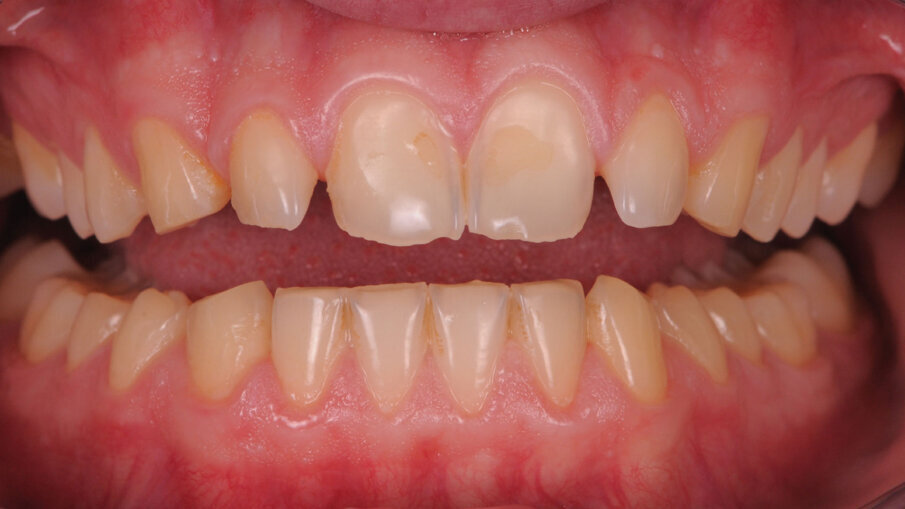

Paziente maschio di anni 26, si presenta alla prima visita con una esplicita richiesta di miglioramento estetico, in quanto non soddisfatto dei suoi denti e di conseguenza del suo sorriso. All’anamnesi riferisce di sorridere poco e con difficoltà, limitando la sua socialità1. Risulta fondamentale in questi casi la fase del colloquio iniziale, per far emergere gli aspetti che il paziente ritiene sgradevoli e cosa invece lo farebbe sentire a suo agio. Si utilizza la fase iconografica dimostrativa con fotografie eseguite su casi simili già finalizzati per mostrare al paziente le fasi cliniche e le possibili soluzioni alle sue richieste. Bisognerà dedicare molto tempo ad ascoltare il paziente, i suoi dubbi e le sue esigenze, capendo da subito le sue aspettative prima di impostare il piano di trattamento. L’esame clinico intraorale, mostra un’arcata superiore con microdonzia a carico degli incisivi laterali 12 e 22, con diastemi e volume ridotto degli elementi canini in proporzione alla dimensione ossea strutturale. Il termine microdonzia2 è spesso abusato, poiché non vi sono dei parametri che la letteratura indica per definire tale situazione, spesso gli elementi microdontici lo sono in rapporto agli altri elementi dentali come in questo caso. Gli elementi 11 e 21, originariamente normo formati, presentano irregolari abrasioni della superficie vestibolare probabilmente causate da tecniche di spazzolamento incongrue che hanno esposto delle isole di dentina vestibolare3 (Figg. 1-3).

Alterazioni dell’anatomia inoltre si evidenziano anche a livello dei margini incisali dove sono evidenti delle micro fratture a carico dello smalto, originate da un probabile sovraccarico occlusale. Andando alla ricerca di una possibile causa di questo tipo di alterazione morfologica, un’attenta analisi dei gruppi posteriori evidenzia anche qui una situazione inusuale, cioè un’evidente riduzione dello smalto della porzione occlusale degli elementi diatorici specificamente dei premolari e dei primi molari, con conseguente alterazione dell’anatomia, mentre un normale sviluppo e una normale conformazione occlusale degli ultimi molari 37 e 47. Completando la visita e concludendo l’analisi con il V sestante si nota una inevitabile abrasione a carico dello smalto degli incisivi inferiori con usura dei canini soprattutto sul lato destro dove il canino in posizione 43 risulta riportare un’abrasione molto importante a differenza del 33 che appare normo conformato (Fig. 4). Emerge quindi che la situazione intra orale mostra alcuni elementi con alterazioni congenite come gli incisivi laterali e altri elementi con alterazioni acquisite di natura erosiva-abrasiva. In entrambi i casi il percorso da seguire è quello di, studiare le forme dentali residue per “reintegrarle” basandosi sugli elementi integri, utilizzati come guida per una riabilitazione “anatomicamente” guidata.